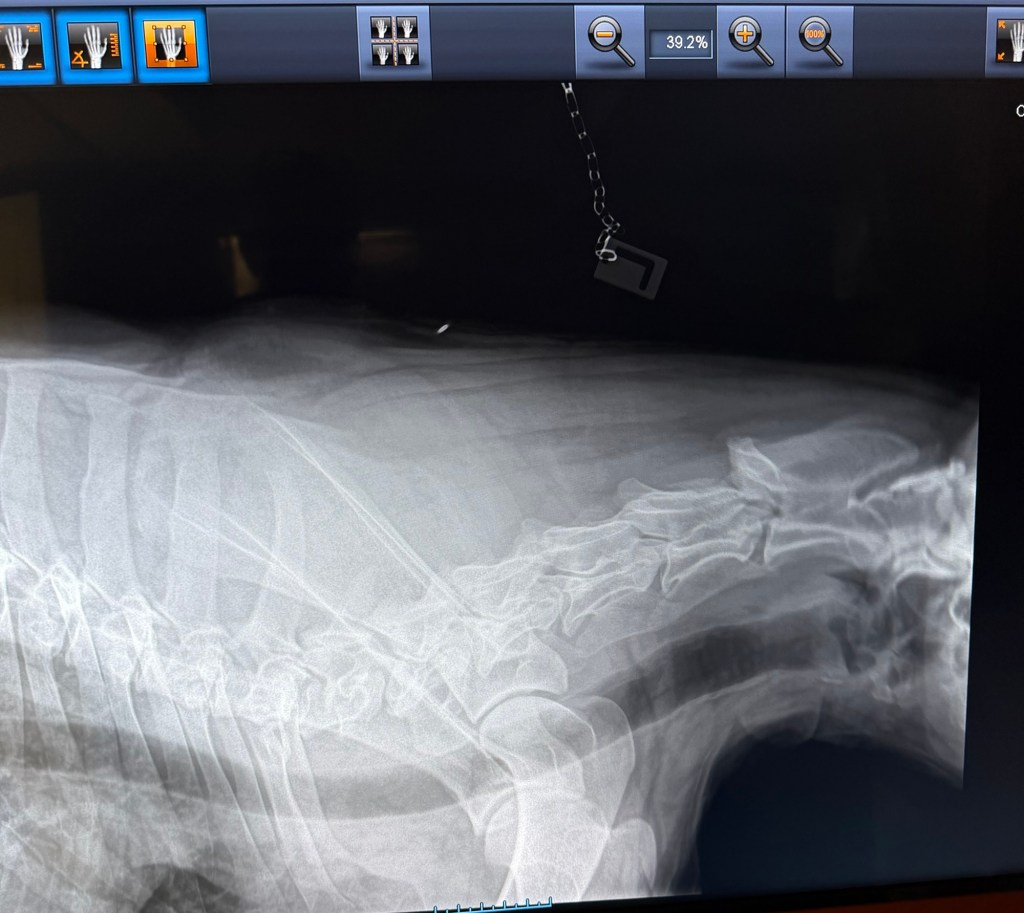

Geri var på ny røntgen nå i november 2025, i en alder av 3år og 8måneder. Dette for å være ansvarlig og forsikre meg om at det ikke blir avl på foreldredyr som har feil utvikling og avdekke svakheter hvis de eksisterer.

Det viste seg å være meget positive resultater (legger ved noen av bildene). Ingen forkalkninger og fremdeles fine albuer, ingen forandring fra 18 måneder HD/AD røntgen til nesten 4års alder. Hun har også en meget fin rygg, og spesielt god og robust lenderygg (bak) som er et fokus område for schæferhunden.